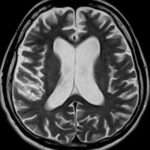

La encefalopatía de Wernicke es un trastorno neurológico agudo que se caracteriza por una tríada clásica de síntomas: confusión, ataxia y nistagmo, los cuales pueden progresar a oftalmoplejía, es decir, debilidad del músculo recto lateral y parálisis de la mirada conjugada. Esta condición resulta de una deficiencia de tiamina (vitamina B1), un nutriente esencial para el metabolismo cerebral adecuado.

El diagnóstico de encefalopatía de Wernicke se confirma típicamente mediante la respuesta clínica rápida al tratamiento con tiamina. Los pacientes con encefalopatía de Wernicke a menudo muestran mejoría significativa en su estado mental y síntomas neurológicos dentro de uno o dos días de iniciar el tratamiento con tiamina. Es crucial comenzar el tratamiento con tiamina sin demora, incluso antes de obtener la confirmación de laboratorio de la deficiencia de tiamina, para evitar daños neurológicos permanentes. Sin embargo, es importante recolectar muestras de sangre antes de la administración de tiamina para confirmar la deficiencia de tiamina como parte de la evaluación y seguimiento del paciente.